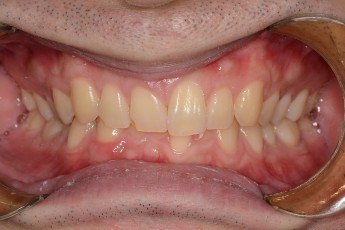

Before

After